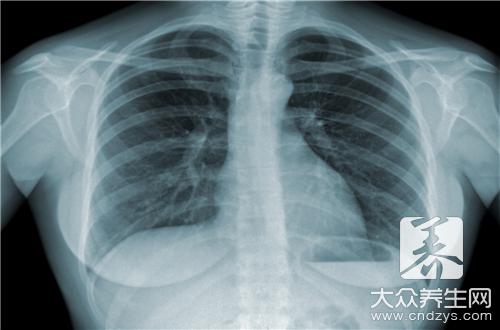

结核病主要是以肺结核最为常见,它主要是因为患者在生活中长期吸烟或者长期工作在一些环境污染比较大的空间中引起的。随着医学技术的发展,在民间有很多可以治疗结核病的偏方,希望患者可以采用一些来治疗结核病,比如通过食用白木耳和黑木耳等药材来达到清肺的作用。